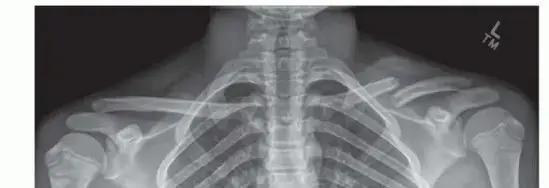

صورة توضيحية لـ كسر عظمة الترقوة: دليل شامل للمرضى في اليمن والخليج العربي مع الأستاذ الدكتور محمد هطيف

• الأشعة السينية (X-ray): تؤكد الأشعة السينية وجود الكسر وتحدد موقعه ونوعه ومدى تشرده (انفصال أجزاء العظم عن بعضها).